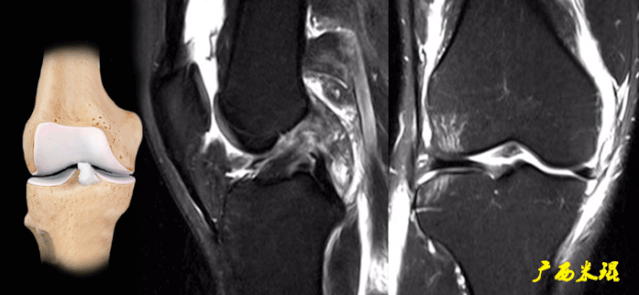

(七)ACL损伤直接征象

1)ACL本身的形态和信号异常:

2)不连续:

有韧带的低信号,但中断不连续。

一般见于新鲜损伤。

3)方向异常(ACL 下垂征):

有较完整的韧带低信号,但方向异常,呈下垂状。

一般见于股骨附着部的陈旧损伤,损伤的ACL下垂并粘附在PCL上。

4)消失:

髁间窝空虚,无韧带信号。

见于较久的损伤,损伤的ACL撕裂较重呈马尾状,无滑膜包裹,逐渐被关节内的酶腐蚀而消失。